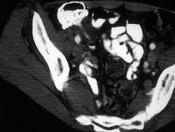

问题 男,42岁,右下腹痛、腹胀半年,无浅表淋巴结肿大,影像检查如图,最可能的诊断是 ( )

选项 A.淋巴瘤 B.结肠癌 C.Crohn氏病 D.肠结核 E.腹膜后纤维化

答案 C